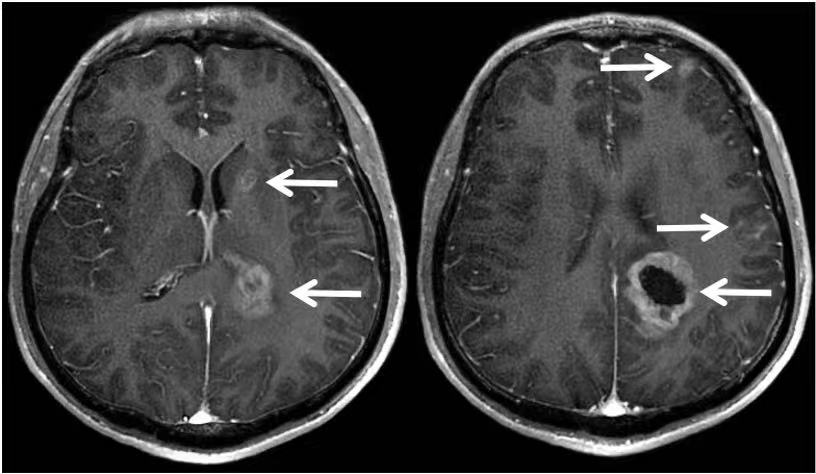

可是好景不长,同年8月,李先生在干活的时候,突然出现头晕,而且逐渐加重,并出现双下肢乏力,腿脚不灵活等症状。紧急去医院复查,做了一个头颅MR,提示:颅内多发异常信号,转移瘤可能性大。

克唑替尼耐药了!无奈,平静的生活不得不再次中断,迎接李先生的是全脑放疗。

奇迹再次发生,在放疗并配合药物治疗之后,颅内转移灶,在持续缩小!在后期的随访中,颅内的病灶一直没有再复发。